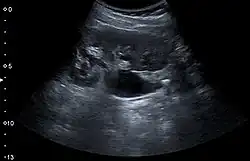

Renal ultrasonography can sometimes be useful, because it gives details about the presence of hydronephrosis, suggesting that the stone is blocking the outflow of urine.[59] Radiolucent stones, which do not appear on KUB, may show up on ultrasound imaging studies. Other advantages of renal ultrasonography include its low cost and absence of radiation exposure. Ultrasound imaging is useful for detecting stones in situations where X-rays or CT scans are discouraged, such as in children or pregnant women.[67] Despite these advantages, renal ultrasonography in 2009 was not considered a substitute for noncontrast helical CT scan in the initial diagnostic evaluation of urolithiasis.[66] The main reason for this is that, compared with CT, renal ultrasonography more often fails to detect small stones (especially ureteral stones) and other serious disorders that could be causing the symptoms.[14]

Renal ultrasonograph of a stone located at the pyeloureteric junction with accompanying hydronephrosis. -